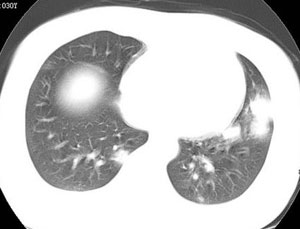

女性,30岁。

病史为胸痛20多天,无畏寒发热,无消瘦,无咳嗽咳痰。总之症状很逍遥。

临床以胸痛待查收住入院。

双肺野可见散在大小不等结节及肿块影,内密度不均匀,边缘部分清,部分欠清,纵隔未见明显肿大淋巴结.右侧胸腔少理积液.结合临床,考虑韦格肉芽肿可能吧,巨淋巴增生,结节病,特殊感染都要考虑.转移瘤临床不象.

多发、内可见含气支气管征,边界不清;纵隔内未内见明显肿大淋巴结。右侧少量胸腔积液。

考虑:1、化脓性肺炎?

2、肺霉菌感染?

本病例特点如下:

1.青年女性,以胸痛20多天就诊,无呼吸道及感染临床症状体征,无原发肿瘤病史;

2.肺ct表现为两肺多发大小不等结节影,大结节位于肺尖部,小结节多位于肺外带胸膜下,大结节内可见支气管充气征,周围可见月晕征(指在结节状或肉芽肿样病灶周围呈环形磨玻璃影),右肺门及腔静脉后可见小淋巴结,右侧胸腔内少量液体。

两肺散在分布大小不等的肿块及结节影,边缘毛糙,有分叶、毛刺,病灶密度不均匀,可见支气管充气相与空泡征。病变大多位于胸膜下,可见胸膜凹陷及胸腔积液。气管腔静脉间可见小结节影。

病人临床仅为胸痛,暂不考虑感染性病变。

考虑多发结节型细支气管肺泡癌。